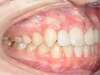

Cas 2 : Description

Tendance prognathisme.Traitement par gouttières.

Avant